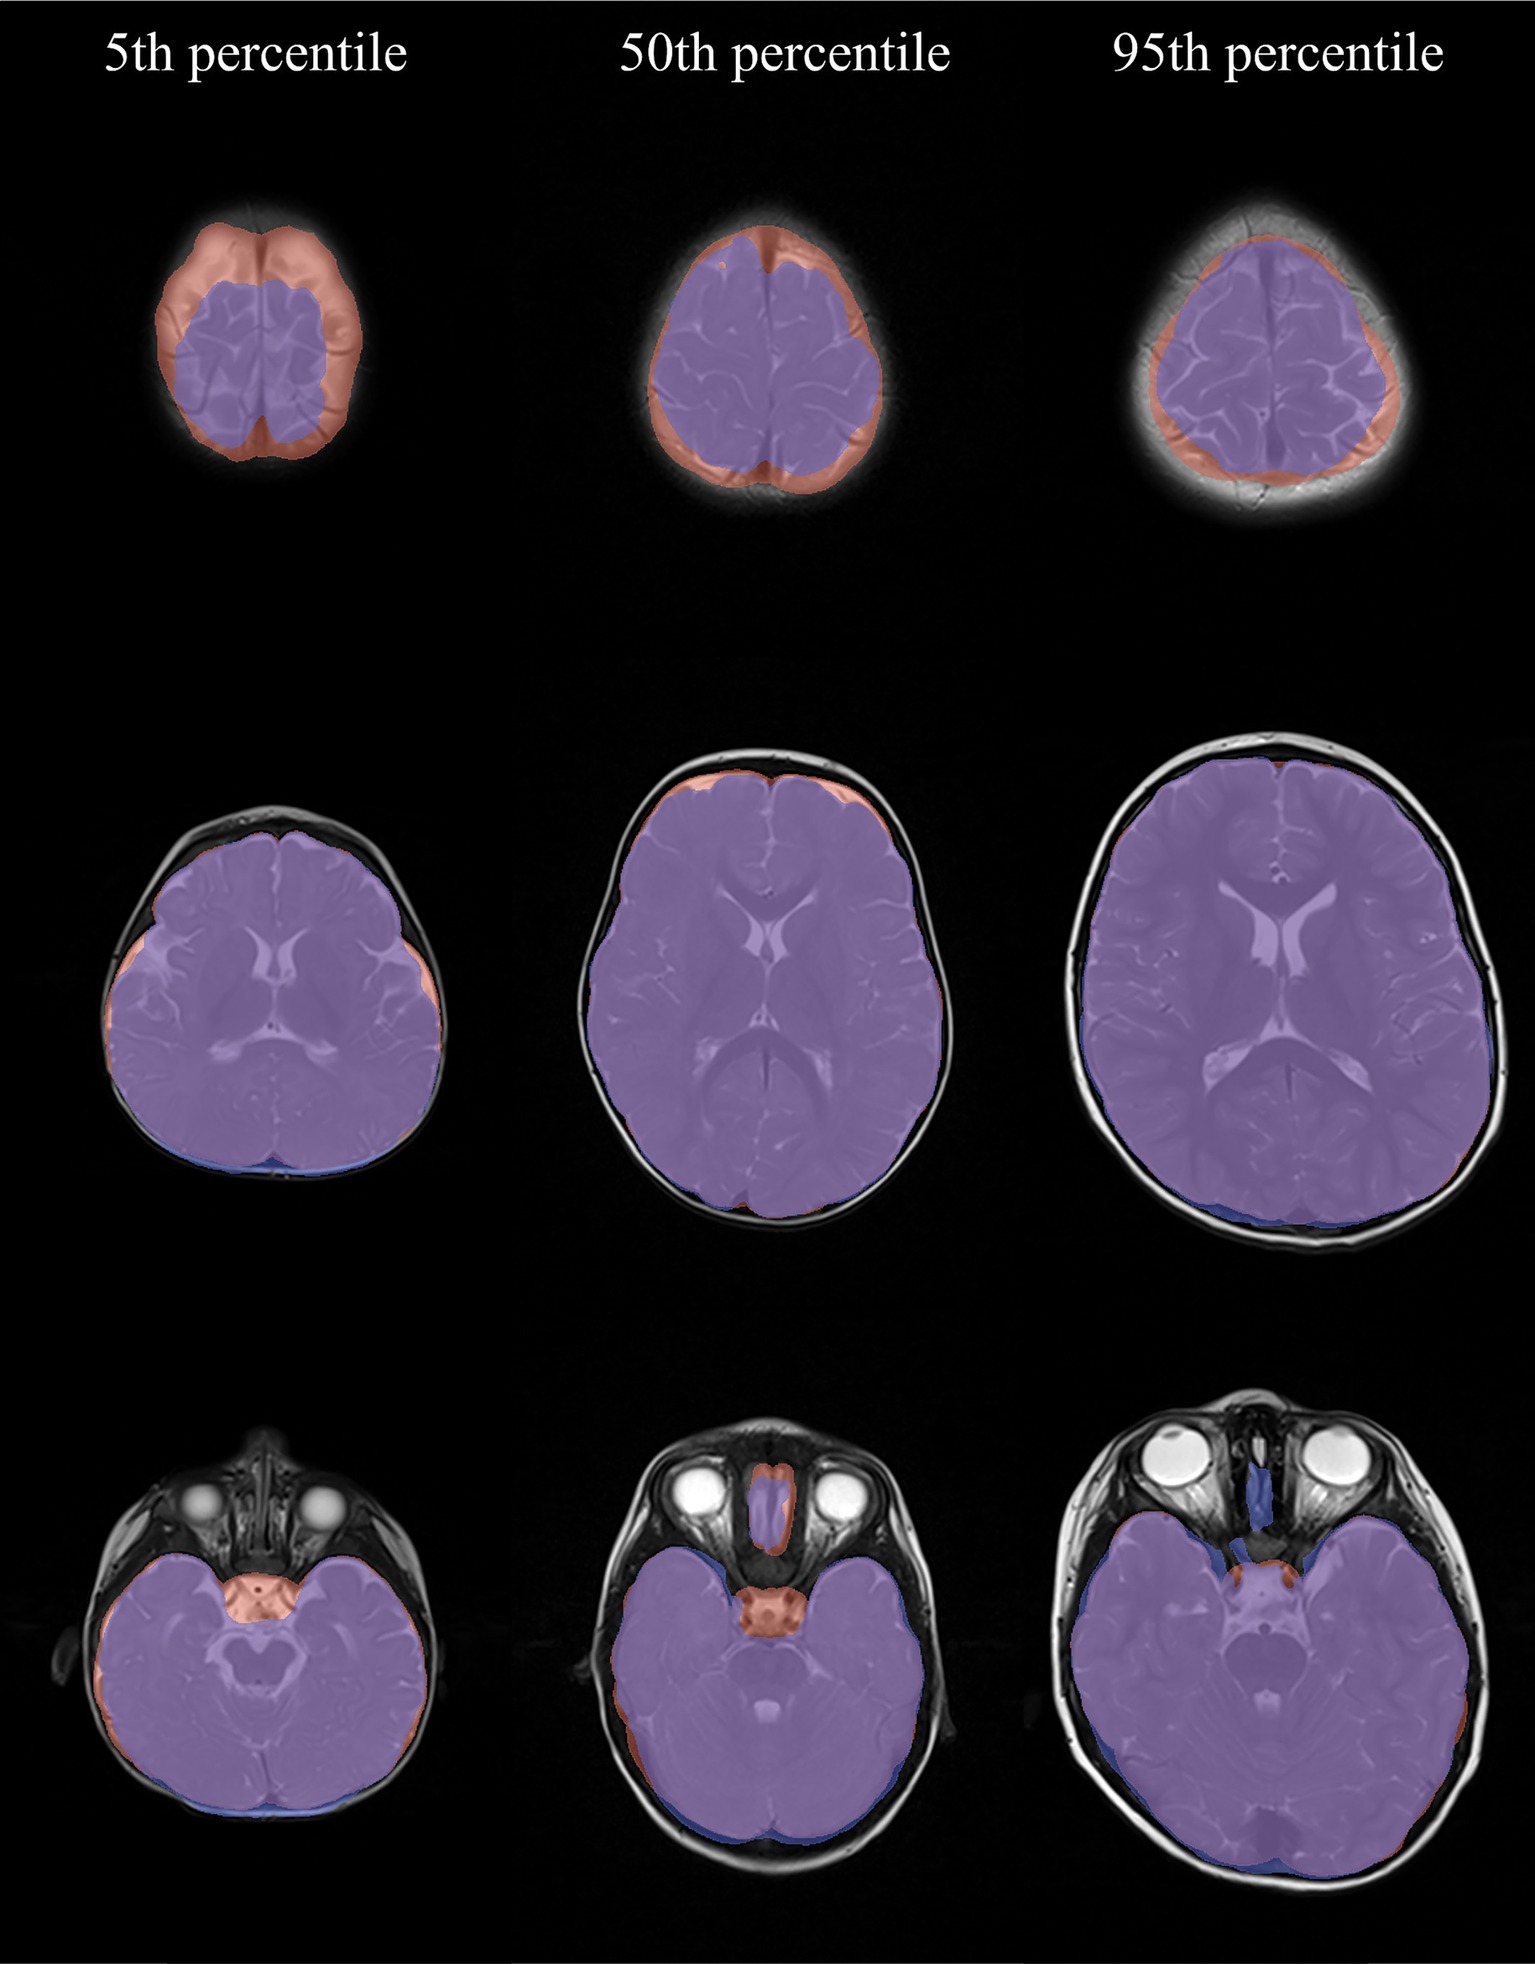

Introduction: For brain maturity assessment of infants aged above six months, T2-weighted MRI scans are recommended. Prior to automated brain tissue analysis, skull stripping is typically applied. However, most skull stripping tools neither focus on T2-weighted scans nor on pediatric cohorts. Here, we present the evaluation results of seven common skull stripping tools in a comparably large pediatric cohort. Methods: This study is based on 199 T2-weighted scans of children under the age of five years retrospectively acquired from the clinical routine at Hannover Medical School. We established a manually labeled ground truth under quality control of a senior neuroradiologist specialized in pediatric neuroradiology and evaluated seven skull stripping tools (BET, ROBEX, HD-BET, HD-BET-fast, SynthStrip, SynthStrip-noCSF and d-SynthStrip). Segmentation performance (Dice score, 95th percentile Hausdorff distance, sensitivity, specificity) and computation time were assessed on non-preprocessed and preprocessed scans (zero padding, contrast enhancement, artifact removal and normalization) as well as in different brain regions. For the best performing model, we manually assessed the top and bottom quartile of segmentations with respect to the integrity of different anatomical brain structures. Results: Only BET, HD-BET, HD-BET-fast profited from data preprocessing. Considering this, all models had median Dice scores between 0.88 and 0.96, with SynthStrip performing best. All models segmented most accurately in the middle axial slices of the brain. Voxel-resampling lowered the performance of all models, except ROBEX. Mean computing times ranged from 2 sec. (BET) to 132 sec. (HD-BET) with SynthStrip requiring 7 sec. per scan. SynthStrip was prone to not entirely including the Sinus sagittalis superior, the upper Cerebrum, the temporal pole, the Cerebellum and the Chiasma opticum / pituitary gland. In contrast, the petrous bone and the skull in the middle axial slices have often been partly included. Discussion: Due to its robustness and quick computation time, we recommend SynthStrip for skull stripping of pediatric T2-weighted MRI scans. We attribute the observed segmentation errors to the partial volume effect, which should be addressed in future research. Limitations of our study include the monocentric setting, the exclusion of pathological cases and the skewed age distribution in our cohort.